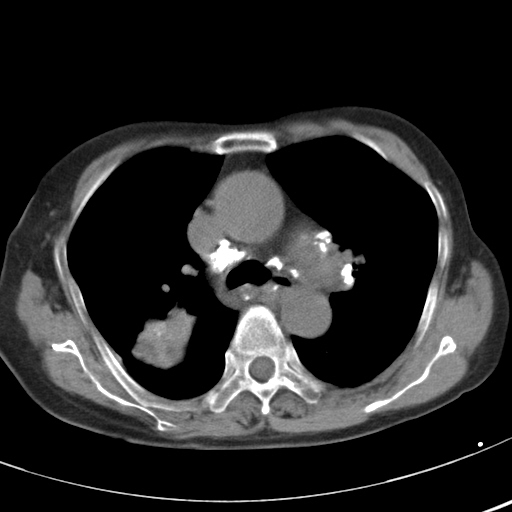

以下是引用hhcckk在2007-3-2 14:51:00的发言:[br]考虑结核球可能性大,依据[br]1病灶在下叶背段,结核的好发部位[br]2病灶内有大量的钙化,纵隔内有大量的淋巴结钙化[br]3重要的是半年前与现在相比无变化,假如是肿瘤的话不会这么‘善良’[br]4病灶周围卫星灶不明显,病灶有毛刺,胸膜凹陷,肿瘤不能完全排除,有条件的话最好做个活检

以下是引用liuyue在2007-3-2 17:15:00的发言:[br]1位置:右上叶后段[br]2性质:大分叶、粗长毛刺、条状斑片状钙化、纵隔多发淋巴结钙化,无强化,故考虑:肺结核灶(陈旧)